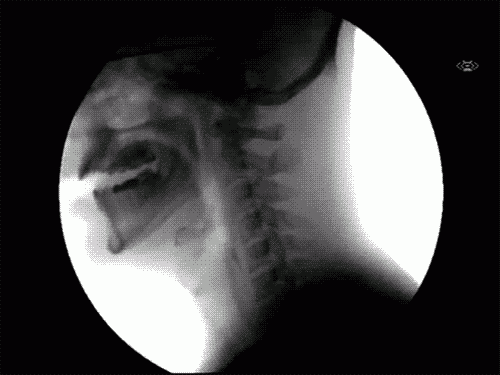

You might have come across numerous studies condemning the drug use and felt safe from addiction, but this is not the only concern when it comes to cocaine. These images will give you a real insight on what is going on inside your body every time you snort a line – other than the possibility of drug dependence. Side effects vary according to the dose and usage frequency.

Regular snorting leads to persistent runny nose, nose bleeds, nasal perforation, loss of sense of smell and lung damage

Difficulty swallowing